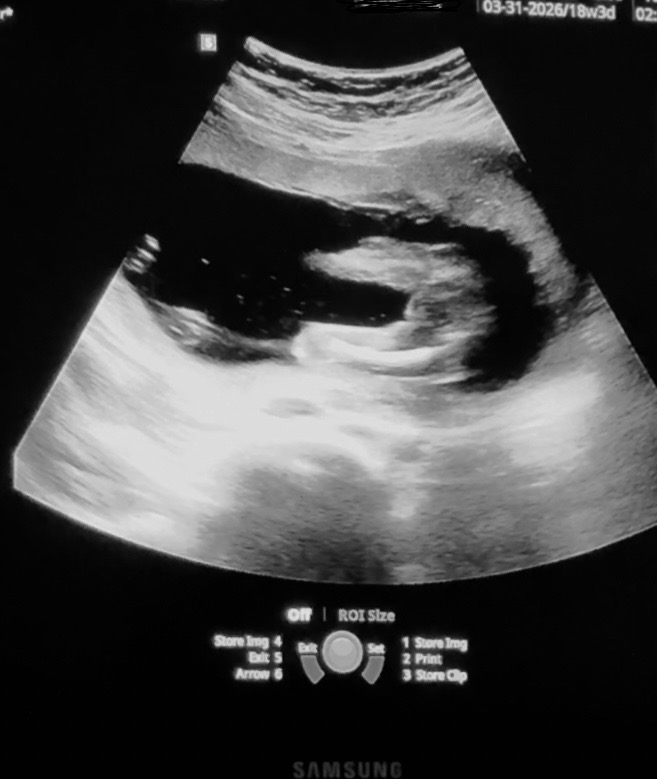

My husband is pushing to wait until the birth to find out gender. I have been on board bc he has wanted this experience of waiting since our first baby and this is our third. We have two girls. However I have been trying to decide to wait with him or find out. I have been inspecting the 18 week ultrasound. The doc tried her best to get this view for the measurement only and avoid revealing any gender. This screen shot is the closest it got to showing anything. What do you see?